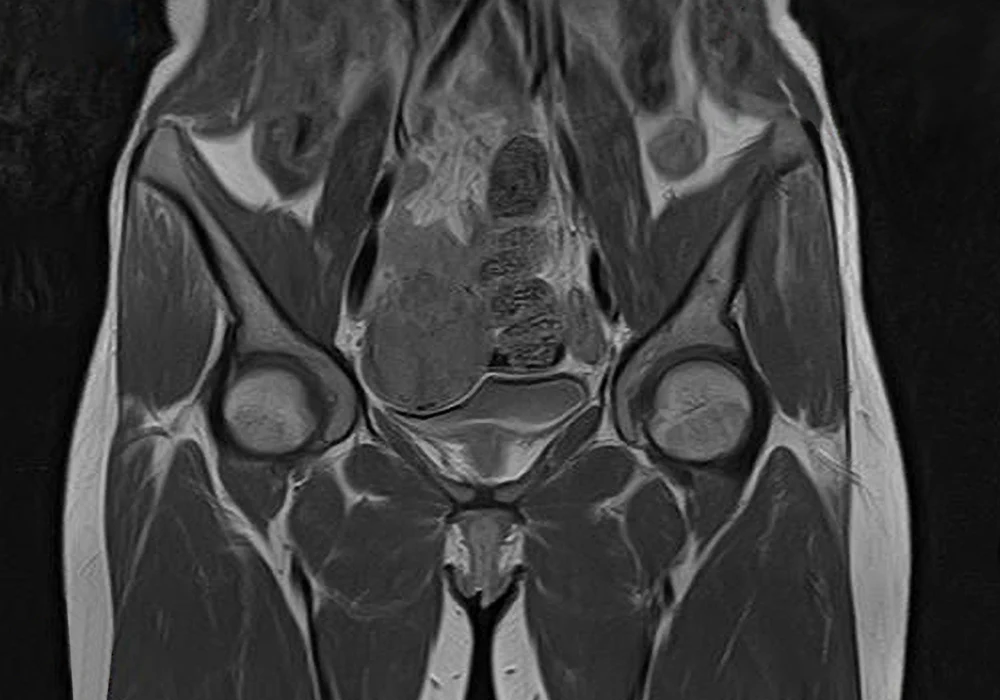

The advent of quantitative MRI techniques marks a transition in the clinical management of uterine cancers, notably endometrial cancer (EC) and cervical cancer (CC). These malignancies, though originating in the same anatomical region, differ significantly in epidemiology, pathology and clinical behaviour. Historically reliant on morphological imaging and histopathological data, oncological diagnostics now benefit from advanced imaging biomarkers that offer functional and molecular insights. Quantitative MRI, incorporating modalities such as Dynamic Contrast-Enhanced MRI (DCE-MRI), Diffusion-Weighted Imaging (DWI) and Magnetic Resonance Spectroscopy (MRS), bridges the gap between non-invasive imaging and personalised treatment strategies.

DCE-MRI allows clinicians to quantify physiological parameters of tissue microcirculation, a process central to tumour biology. Parameters such as Ktrans, Ve and Vs offer key insights into perfusion and vascular permeability, providing vital clues about tumour aggressiveness. These biomarkers have proven superior to conventional T2-weighted imaging for detecting critical features like myometrial or cervical invasion in EC and CC.

DWI, particularly with high b-value sequences and the Intravoxel Incoherent Motion (IVIM) model, is instrumental in differentiating between benign and malignant lesions and assessing therapeutic response. Apparent diffusion coefficient (ADC) values, derived from DWI, tend to be lower in aggressive or poorly differentiated tumours due to increased cellularity that restricts water movement.